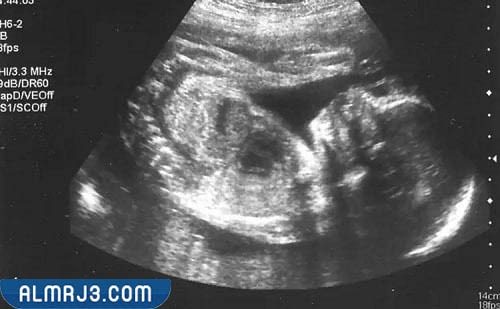

- فحص السونار: تساعد الأشعة فوق الصوتية في التعرف على نوع الجنين من خلال عمل مسحة بسيطة على البطن حتى يظهر الجنين وهو داخل الرحم؛ ومن ثم معرفة حالته الصحية.

- يتمكن الطبيب من معرفة نوع الجنين باستخدام أجهزة السونار خاصة، وأن أعضاء الجنين التناسلية تكون قد اكتملت في هذه الفترة.